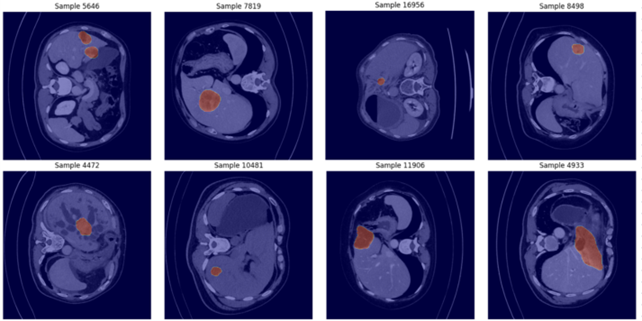

Preprocessing was necessary to prepare the dataset, which consisted of 3D volumes, for training. A verification pipeline was developed to ensure consistency between CT volumes and their corresponding segmentation masks of tumor regions (ground truth), as shown in Fig. 1. Each CT–mask pair underwent validation for dimensional alignment, slice count, file integrity, and the presence of annotated lesions. The pairs identified as invalid or mismatched were excluded from further analysis. The results of this verification process were documented in a metadata CSV file, which subsequently served as an index for all experimental procedures. This preprocessing pipeline produced a reliable and balanced dataset of 2D liver tumor slices, enabling efficient experimentation with different segmentation architectures.

Refer to caption

Figure 1: CT slice samples with ground truth.